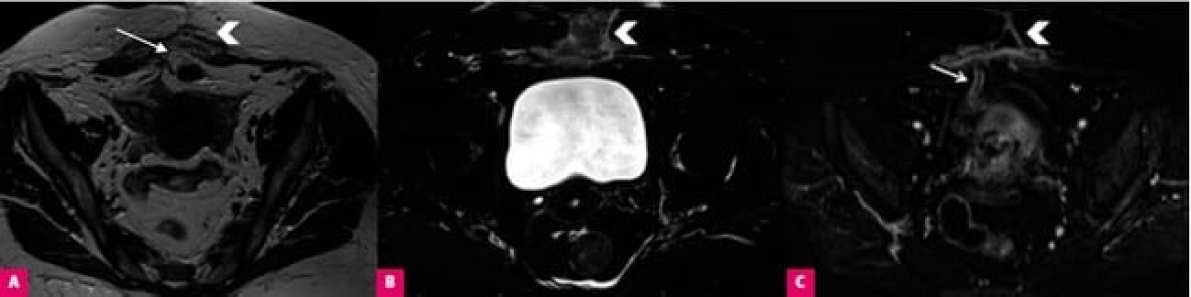

Наиболее часто используемые методы визуализации после тазовой хирургии — ультразвуковые (трансабдоминальные и трансвагинальные) исследования, магнитно-резонансная томография (МРТ) и компьютерная томография (КТ).

В то время как ультразвук является стандартным методом, который использует оценку в сером или цветном доплеровском режиме, выбор МРТ и КТ должен определяться конкретными показаниями для данного теста.

Если изображение, полученное с помощью ультразвука, неоднозначно, расположено за пределами доступа датчика или скрыто кишечными газами, следует провести компьютерную томографию, особенно в случае острых заболеваний брюшной полости и таза.

КТ доступна в большинстве центров и хорошо переносится значительной частью пациенток, даже в критическом состоянии. Этот быстрый тест также позволяет провести всестороннюю оценку органов брюшной полости и малого таза путем получения дополнительной информации. Например, врач может изучить кровоток, функцию почек или увидеть перфорацию кишечника.

Стандартное компьютерное сканирование должно включать оценку состояния брюшной полости и таза. Если не указано иное, тест должен проводиться с внутривенным контрастным веществом (контрастирование). Сканирование должно быть выполнено до и после введения контраста, в артериальной и портальной фазах (30-40 секунд и 70-80 секунд задержки сканирования после введения контрастного вещества, соответственно).